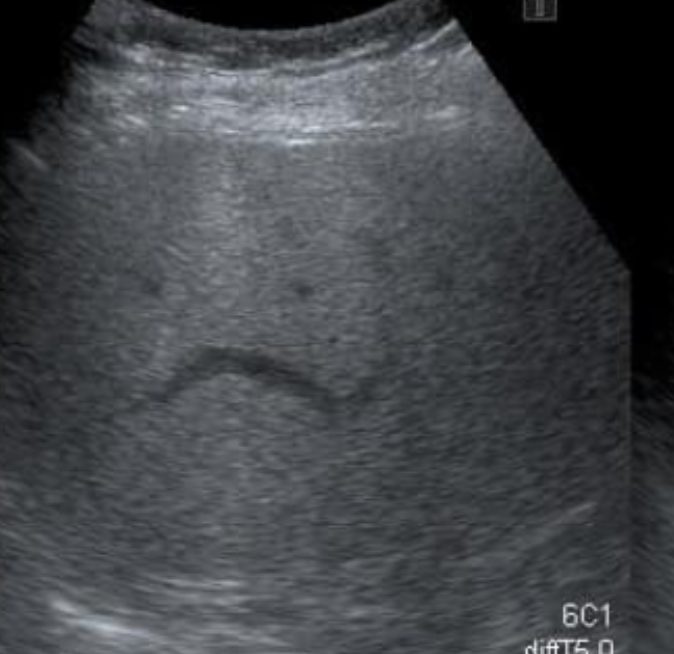

脂肪肝已成为大马人的头号健康威胁,根据数据显示,大马每3名成年人中就有1人患有脂肪肝,患病率高达约33%,且随着饮食西化更有年轻化的趋势。每当健检报告出现“红字”时,许多民众的第一反应常是:“是不是要吃保肝药?”